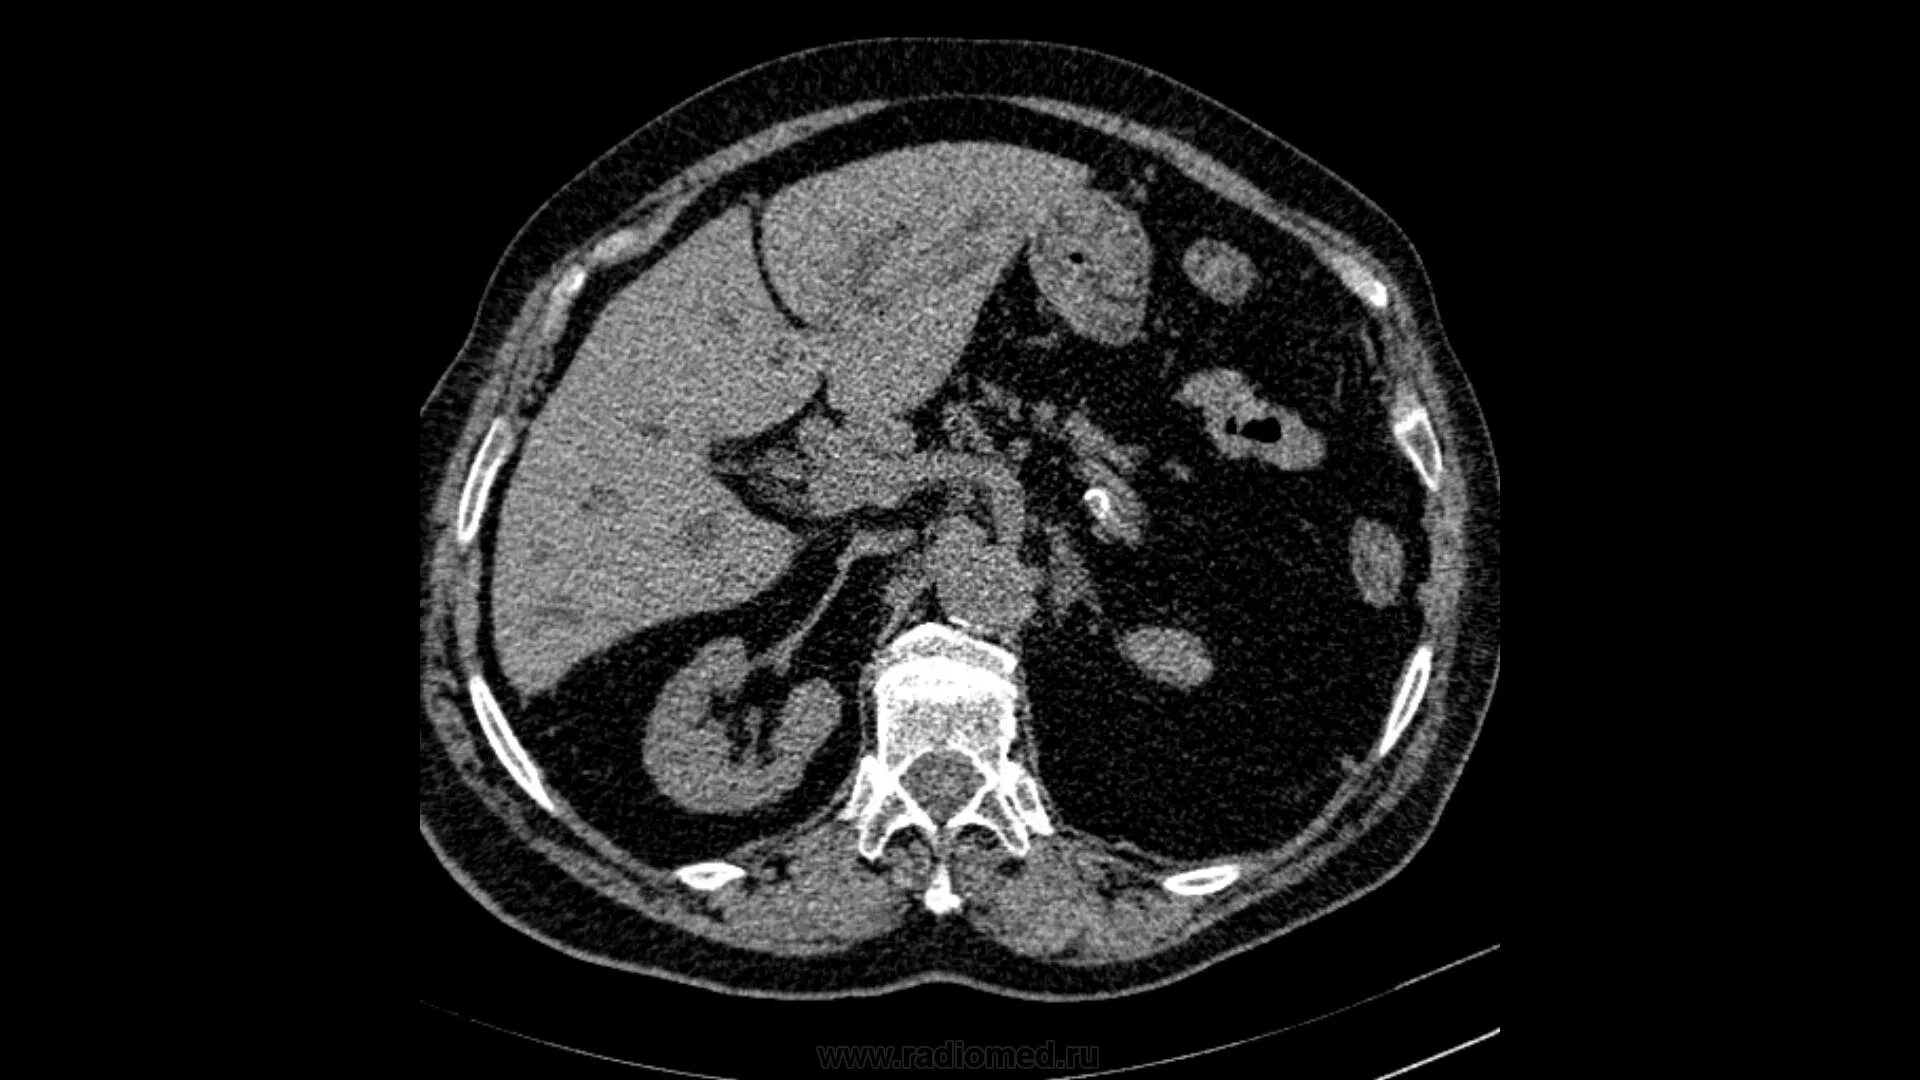

Цирроз на кт